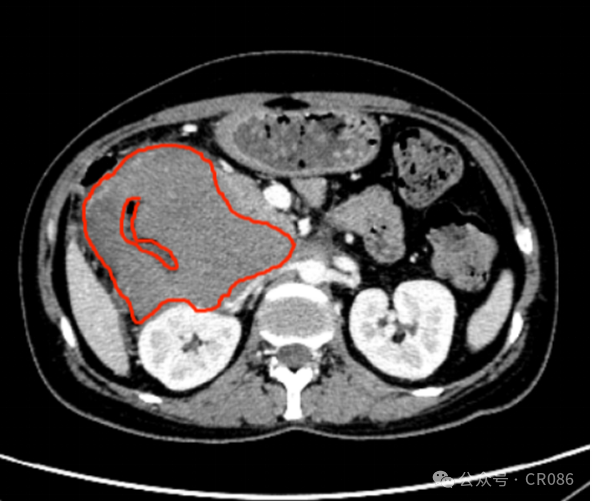

11月,袁姐住进了病房,做了CT检查,肿瘤最大横截面大小:9.9*9.5cm。妥妥一个“小柚子”,这么巨大的肿瘤真是不由让人倒吸一口凉气,难怪医生已经放弃努力。

2024.11.06 红色圈出部分为肿瘤。